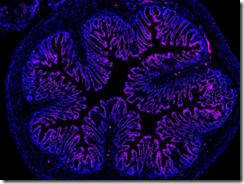

医療・健康 LED光と錫ナノ粒子を用いた新たながん治療法(LED Light Blasts Cancer Cells and Spares Healthy Ones)

2025-10-09 テキサス大学オースチン校 (UT Austin)テキサス大学オースティン校とポルト大学の共同研究チームは、LED光とスズ酸化物ナノフレーク(SnOx)を組み合わせ、がん細胞のみを選択的に死滅させる新たな光治療法を開発し...